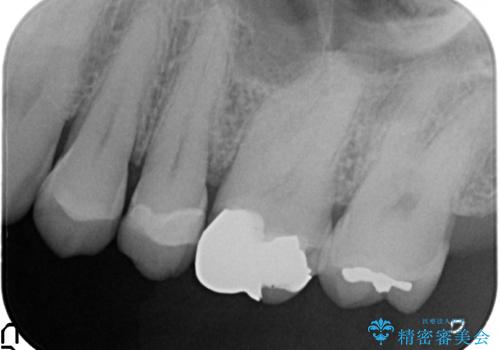

- 左上6番目の歯が欠けてしまったので診て欲しいといらっしゃった方の症例です。

左上6番目は銀歯・虫歯を除去後、オールセラミッククラウンにて補綴を行いました。

左上7番目も虫歯だったため、銀歯・虫歯を除去後、セラミックインレーにて修復を行いました。